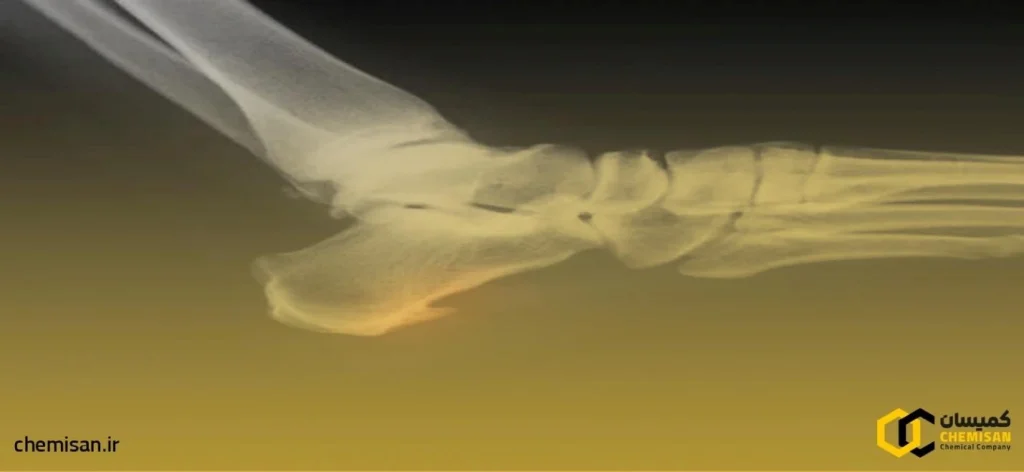

خار پاشنه به رسوب کلسیمی گفته می شود که به شکل زائده ی استخوانی در زیر استخوان پاشنه (کالکانئوس) تشکیل می گردد. این زائده با چشم قابل مشاهده نیست و تشخیص آن نیازمند تصویر برداری با اشعه ایکس است. عوامل متعددی از جمله فشار مداوم بر پاشنه ناشی از فعالیت هایی مانند دویدن یا پریدن بر سطح سخت، ایستادن طولانی مدت، صافی کف پا، دیابت یا افزایش سن می توانند به ایجاد خار پاشنه منجر شوند.